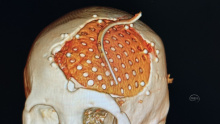

除了PEEK 钛网 本次用了超高分子量聚乙烯 颅骨修补

脑血管-烟雾病